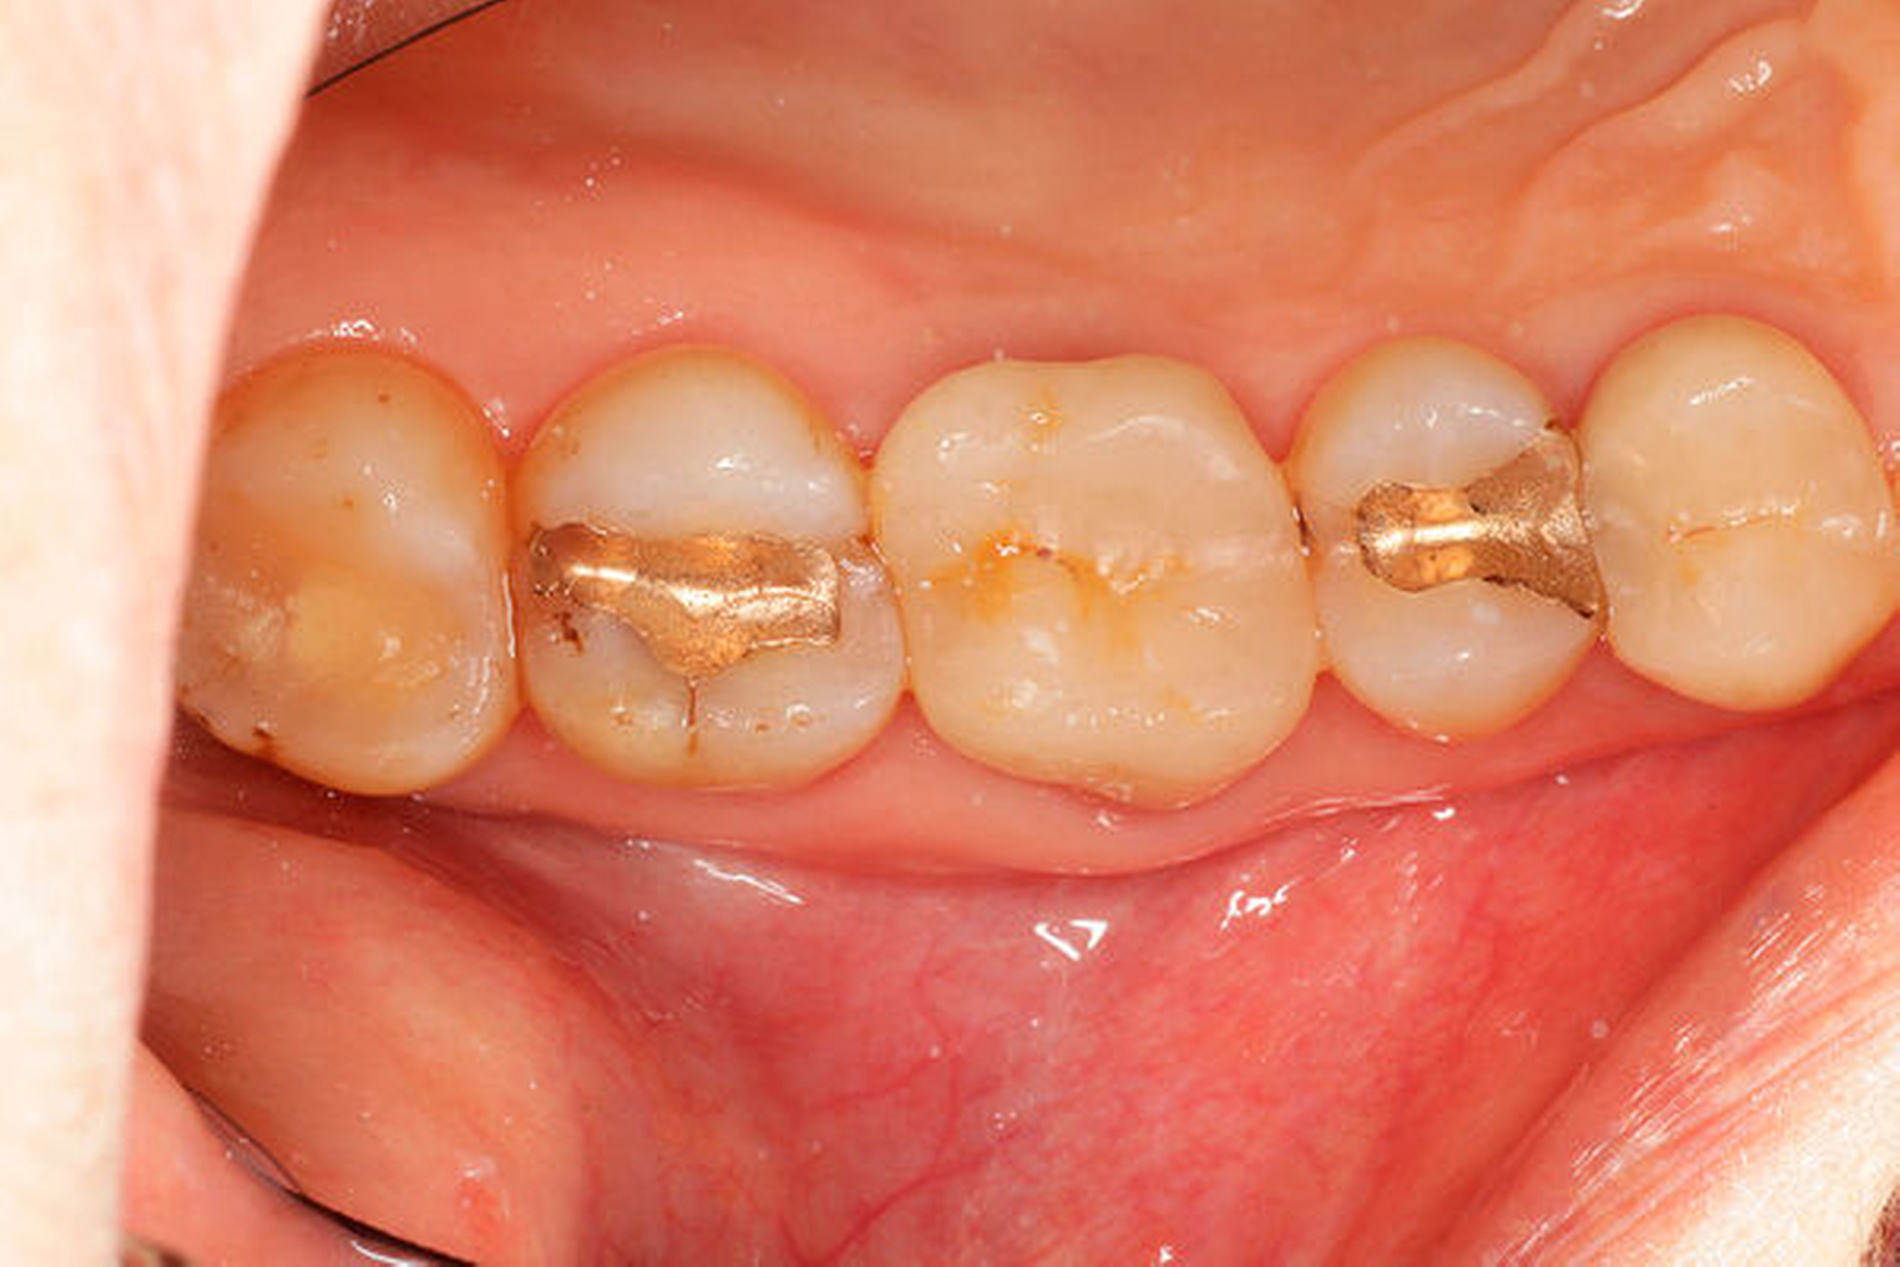

Eine 54-jährige Patientin stellte sich 2018 in der Praxis vor, nachdem sie beim Essen ein Goldinlay an Zahn 16 verloren hatte. Sie klagte über eine Aufbissempfindlichkeit des Zahnes sowie über das Gefühl einer Lockerung. Klinisch zeigte sich eine tiefe Fraktur des Zahnes in mesiodistaler Richtung. Nach klinischer und röntgenologischer Diagnostik wurde die Patientin über die Möglichkeit der Extraktion mit anschließender prothetischer Versorgung der Lücke und den aufwendigen Erhaltungsversuch mittels endodontischer Behandlung des Zahnes samt Amputation der palatinalen Wurzel aufgeklärt. Die Patientin war sehr motiviert und entschied sich für den Erhaltungsversuch.

So erfolgte nach endodontischer Behandlung des Zahnes die Amputation der palatinalen Wurzel und die Versorgung des Zahnes mit einer Vollkrone. Die Situation an 16 ist seitdem stabil, allerdings zeigen sich auch hier palatinal erhöhte Sondierungstiefen, die röntgenologisch mit einem progredienten Knochenabbau im Bereich der Furkation zu korrelieren scheinen. Die Patientin gibt an, mit der Reinigung des Zahnes keine Probleme zu haben, möglicherweise ist diese jedoch durch die Einziehung im Bereich der Furkation vor allem palatinal erschwert. Die Patientin wurde daraufhin instruiert, wie sie die häusliche Mundhygiene in den schwer zugänglichen Bereichen intensivieren und verbessern kann.